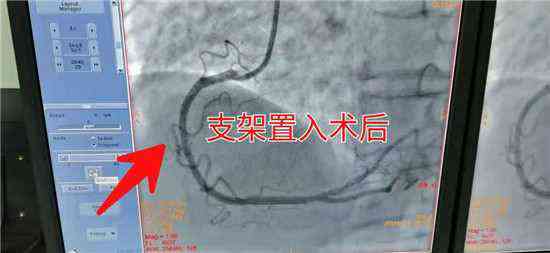

近日,新邵縣人民醫(yī)院急診科接來一位85歲,胸痛、胸悶的老人,根據(jù)其癥狀及臨床表現(xiàn),醫(yī)生初步診斷為急性心肌梗死。病情就是軍令,迅速為患者完成各項檢查,第一時間送入介入科搶救。五分鐘內(nèi)各路人員迅速到位,迅速給患者擺體位、上監(jiān)護、消毒、鋪巾、穿刺、送管、造影一氣呵成。冠脈造影顯示患者為急性下壁心肌梗死,需緊急為患者置入支架 打通血管。時間就是心肌!關(guān)鍵在此一搏,在家屬的積極配合下,迅速談話簽字,一切準(zhǔn)備就緒。

介入醫(yī)生輕舞導(dǎo)絲、細(xì)捻導(dǎo)管、聚精會神,半小時內(nèi)一枚冠脈支架有條不紊的送到了老人病變血管部位,為患者冠脈血管架起了一座圓形橋梁。堵塞的血管道路通了,心肌得到了有效的灌溉,血液歡快的流淌著,唱著生命的歌。